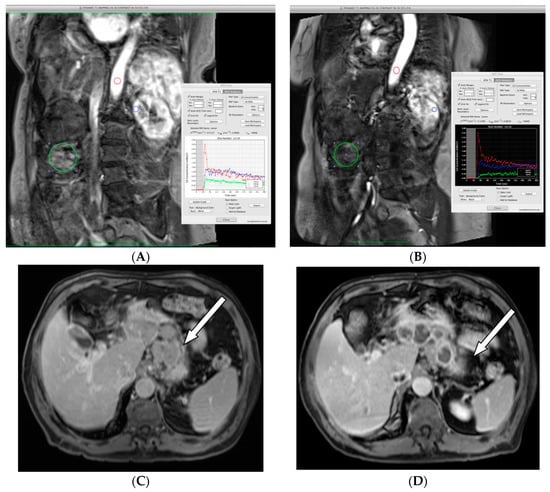

3.4. Pharmacodynamic Assessments